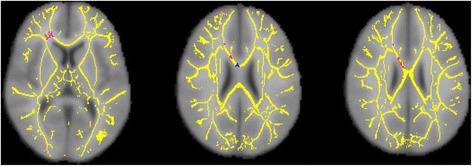

Results: In this study, 17 youth with OCD and 19 healthy control subjects, ages 10 to 19 years, underwent DTI on a 3T Siemens scanner. DSM-IV diagnoses were established with standardized interviews, and OCD symptom severity was evaluated using the Children's Yale-Brown Obsessive-Compulsive Scale (CY-BOCS). Voxel-wise analyses were conducted on data processed with tract-based spatial statistics (TBSS) to derive measures of fractional anisotropy (FA), axial diffusivity (AD), radial diffusivity (RD), and mean diffusivity (MD). OCD patients had significantly lower FA in seven WM clusters, with over 80% of significant voxels in bilateral frontal cortex and corpus callosum (CC). There were no regions of significantly higher FA in patients compared with controls. Patients also had significantly higher RD in right frontal cortex and right body of the CC. Earlier age at onset of OCD correlated significantly with lower FA in the right thalamus and with higher RD in the right CC. FA and RD were not significantly associated with symptom severity.

Conclusions: These findings point to compromised WM integrity and reduced myelination in some brain regions of children with OCD, particularly the CC and fiber tracts that connect the frontal lobes to widespread cortical and subcortical targets. They also suggest that age at onset may be a moderator of some of the WM changes in pediatric OCD.